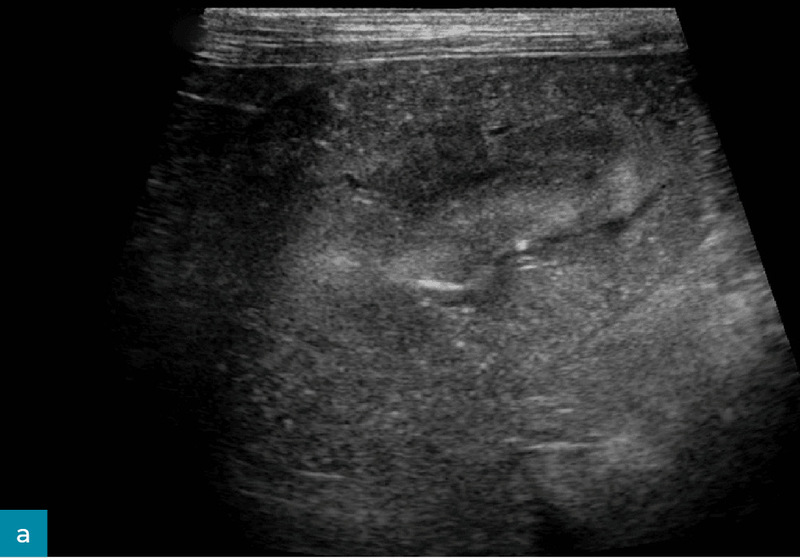

Zmniejszone zróżnicowanie korowo-rdzeniowe

Wyraźne zróżnicowanie między korą a rdzeniem nerki wynika z wyższej gęstości komórkowej w korze oraz większej zawartości płynów w rdzeniu nerki (ryc. 7).15 Wraz ze zwyrodnieniem i utratą zdolności zatrzymywania płynów w rdzeniu nerki echogeniczność rdzenia stopniowo wzrasta, co prowadzi do utraty zróżnicowania między korą a rdzeniem.15

Ryc. 7. Obraz w projekcji strzałkowej prawej nerki kota, ukazujący wyraźnie zmniejszone zróżnicowanie korowo-rdzeniowe, a także hiperechogeniczność kory nerki i jej nieregularne brzegi.